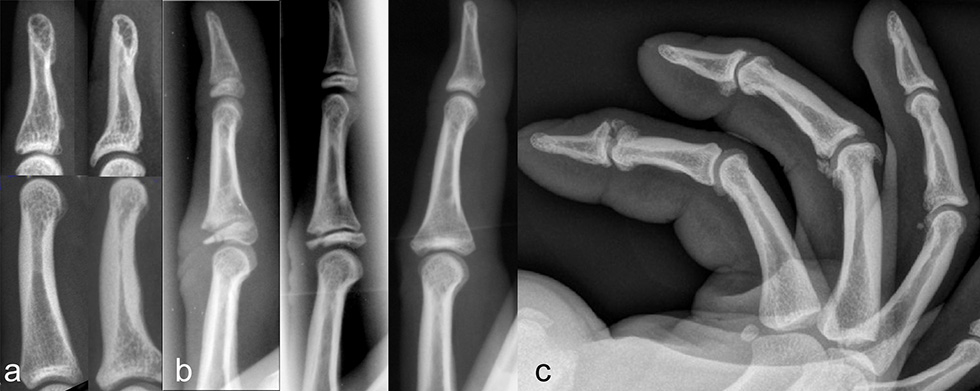

Figure 2

Finger flexor tendon sheath (A) with complete disruption of the A2 and the A3 pulley, partial disruption of the A4 pulley leading to bowstringing of the deep (FDP) and the superficial (FDS) flexor tendons. Ultrasound view of the normal anatomy (B) and of a disrupted A2 pulley (C) with an apparent bowstringing of the flexor tendons. A pulley protection ring (D) brings the flexor tendon back to normal position. Properly applied pulley tape (E) prevents flexion of the PIP joint of more than 80°.

The diagnosis of a pulley disruption is based on the history (pop or snapping sound) and on clinical examination, where a painful flexor tendon bowstringing can be palpated during resisted finger-flexion. The lift-off or bowstringing of the tendon visualised by ultrasound [21, 22] or a magnetic resonance imaging (less accurate) confirms the diagnosis. The treatment recommendations are controversial as some hand surgeons still treat single pulley-disruptions with reconstruction [23]. However, most accept treating single pulley-disruption conservatively eversince Schöffl [24] showed that even with non-operative management no objective or subjective functional loss occurred. Non-operative treatment is generally functional. The healing-time is between 2 to 3 months and full load-bearing can be expected after 4–6 months.

We recommend the use of a special pulley protection ring (fig. 2) designed to protect the neuro-vascular bundles while allowing an adequate reposition of the tendon without compromising circulation within the finger. After two months, the ring is replaced by a pulley protection tape (fig. 2). To take strain off the healing pulley it is applied around the PIP-joint and inhibits flexion of that joint to more than 80° above which pulley load becomes particularly high [17, 19]. With this treatment regimen we were able to reduce the initial bowstringing at the A2-pulley to about 50% and at the A4-pulley to about 40%. If the injury is left untreated or protected only with a tape the amount of bowstringing remains the same. If, however, two or even more pulleys are disrupted (for instance A2 an A3 or A2, A3 and A4-pulley), the amount of bowstringing increases substantially leading to a loss to the active flexion range of motion of the finger and a reconstruction of the ligament has to be considered. This can be performed with a graft from the extensor retinaculum or a free tendon graft. The results of such interventions are generally good and do not differ much between techniques [13, 25, 26]. However, whether all these patients need a reconstruction at all is still being debated. We have seen a series of patients with multiple pulley ruptures who returned to their previous climbing level without restriction except for a small loss of flexion range of motion. It has to be taken into consideration that pulley reconstruction leads to a rehabilitation time of several months.